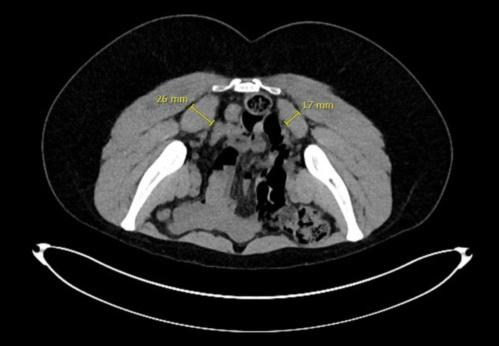

图:梨状肌综合征患者CT可发现双侧梨状肌不对称肥大

目前梨状肌综合征的诊断主要还是依靠医生仔细的特殊体格检查,以及CT或核磁共振的结果。这个病的临床表现很容易与腰椎间盘突出、髋关节疾病相混淆,因此建议患者需到骨关节专科医生这里就诊。